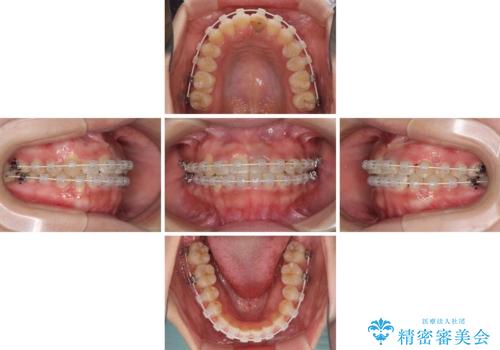

- 矯正装置

- 審美装置

- 治療期間

- 2年2ヶ月

インビザラインでの矯正治療も十分に対応可能でしたが、自己管理の煩わしさから、ワイヤー矯正を行うこととしました。